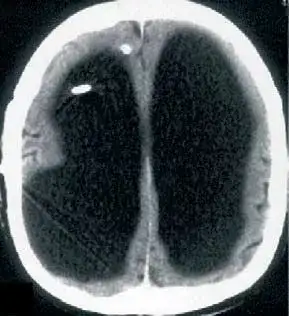

2007 年,《柳叶刀》颁发了一名 44 岁法国男人,因为无诱因左下肢无力,间歇性爆发就诊的病例。大夫查抄他的下肢发现没有异常,思疑是中枢神经系统的问题。于是做了个 CT,成果显示,他有极严重的侧脑室扩张,换句话说,他的脑子只有表层。

这名男纸在出生 6 个月的时辰,因为不明原因的脑积水行脑室分流术,到 14 岁时移除导管及支架。他的大脑在长时候脑积水的侵蚀下,90%已经消逝,IQ 测试只有 75。但他依然正常糊口正常工作,经由过程了本地的公事员测验,在约 30 岁时成婚,已育有一子一女,后代均体健,无神经系统相关疾病等。